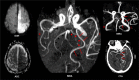

Fetal-type or fetal posterior cerebral artery (FPCA) is a variant of cerebrovascular anatomy in which the distal posterior cerebral artery (PCA) territory is perfused by a branch of the internal carotid artery (ICA). In the presence of FPCA, thromboembolism in the anterior circulation may result in paradoxical PCA territory infarction with or without concomitant infarction in the territories of the middle (MCA) or the anterior (ACA) cerebral artery. We describe 2 cases of FPCA and concurrent acute infarction in the PCA and ICA territories-right PCA and MCA in Patient 1 and left PCA, MCA, and ACA in Patient 2. Noninvasive angiography detected a left FPCA in both patients. While FPCA was clearly the mechanism of paradoxical infarction in Patient 2, it turned out to be an incidental finding in Patient 1 when evidence of a classic right PCA was uncovered from an old computed tomography scan image. Differences in anatomical details of the FPCA in each patient suggest that the 2 FPCAs are developmentally different. The FPCA of Patient 1 appeared to be an extension of the embryonic left posterior communicating artery (PcomA). Patient 2 had 2 PCAs on the left (PCA duplication), classic bilateral PCAs, and PcomAs, and absent left anterior choroidal artery (AchoA), suggesting developmental AchoA-to-FPCA transformation on the left. These 2 cases underscore the variable anatomy, clinical significance, and embryological origins of FPCA variants.